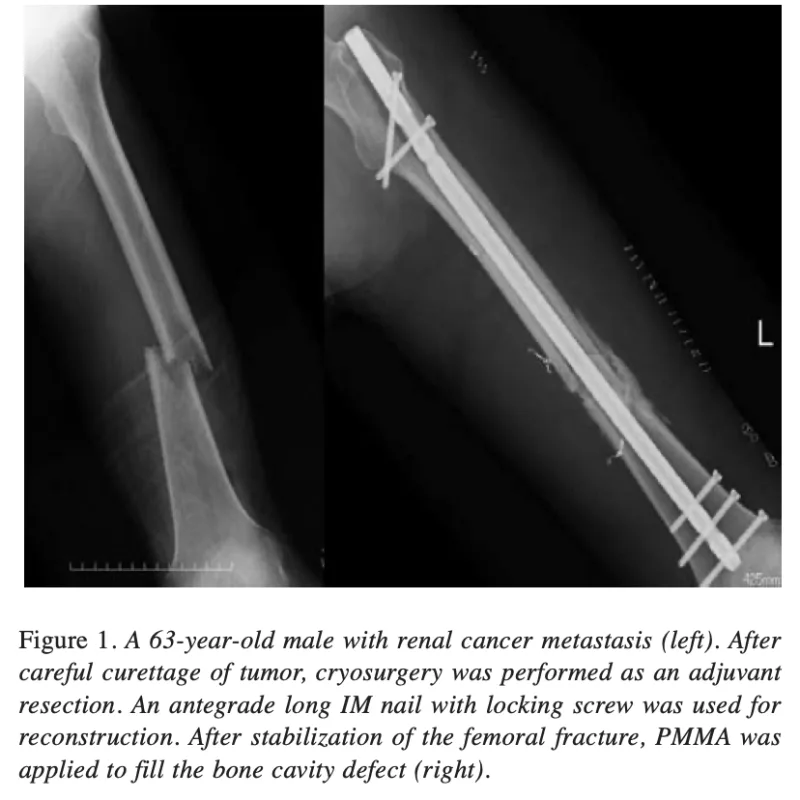

大腿骨骨幹部骨折の患者さんは, 2か月前から大腿部痛が続いており, 昨晩, 立ち上がった際に突然激痛で動けなくなったとのこと.

X線では骨幹部中央に骨溶解像があり, 癌の骨転移あるいは悪性骨腫瘍が疑われました. 既往に癌がないため, 原発巣検索として全身造影CTをオーダーしました.